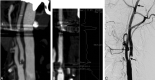

Fig 2.

A, Stenosis measurement levels marked to CTA MIP images according to NASCET. Dental filling artifacts are shown. B, Vessel analysis method in determination of the grade of stenosis. Dental filling artifacts are shown. C, DSA image.